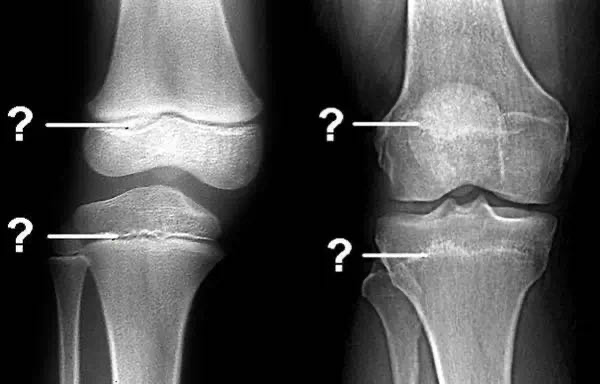

其实最主要的还是要看骨骺有没有闭合。有的人成年后换个环境又长了几厘米,很可能是他的骨骺还没有闭合,换个环境改善了他的睡眠、营养、运动等各方面,于是下肢很给力地又“窜”高了些。

所以成年并不是长高的决定性因素,骨骺才是。那么,如何知道自己的骨骺有没有闭合呢?很简单,去医院拍个片就一目了然了。

如果骨骺已经闭合了,就不要想着为了增高而去打个激素、吃个药、跑个步、跳个高、断个骨(而且断骨增高手术风险非常大,我国卫生部规定:肢体延长术是一项骨科临床治疗技术,适应症为先天畸形、外伤、肿瘤、感染等原因所致的骨缺损或肢体不等长,以及因疾病引起的肢体畸形,严禁用于美容项目)......春雨君残忍地告诉你,那都是徒劳的。虽然外形很重要,但内在品质同样重要,人格魅力同样可以让人闪闪发光,或者换句话安慰自己说:浓缩的都是精华啊!